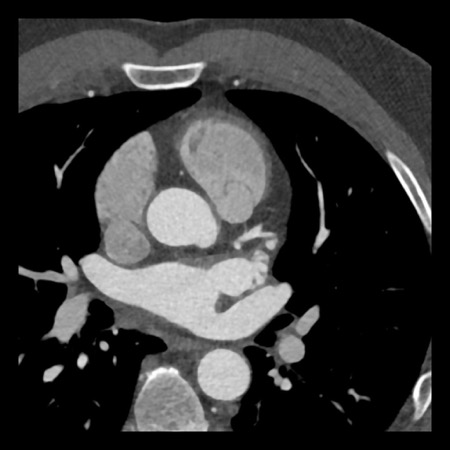

case 3 – Calcium score 0 and severe stenoses.

First, scroll through the CTA images.

How would you describe the findings on the coronary CTA?

The findings are:

- The total calcium

score of 0 indicates the absence of calcified plaque in the coronary

tree. - Severe stenosis

(70-99%) in the mid LAD and D2 branch.